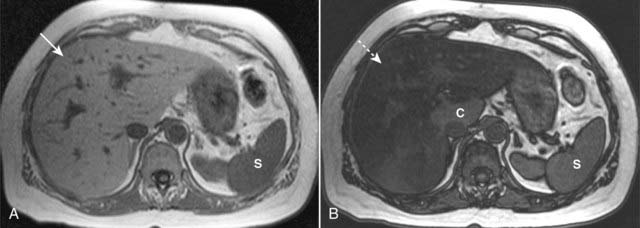

image

Figure 18-28 Fatty liver, MRI.

Using a phenomenon called chemical shift imaging to detect the presence of microscopic, intracellular lipid present in a fatty liver, MRI is the most accurate imaging modality in identifying a fatty liver. Chemical shift relates to the way that lipid and water protons behave in the magnetic field. A, The liver (solid white arrow) appears normal, brighter than the spleen (S). B, This is called an opposed-phase image, and it demonstrates marked signal loss (signal dropout) throughout the liver (dotted white arrow), indicating a fatty liver. Most of the liver is now darker than the spleen (S), except for the caudate lobe (C), which is normal.

image MRI is the most accurate modality in the evaluation of a fatty liver, using a phenomenon called chemical shift imaging to detect the presence of microscopic, intracellular lipid present in such a liver. Chemical shift relates to the way that lipid and water protons behave in the magnetic field (Fig. 18-28).